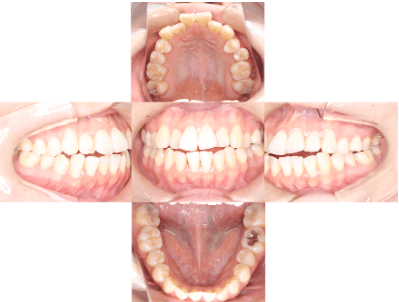

After

治療後

• 初診時年齢:25歳

• 主訴:開咬

• 診断:舌癖を伴う歯性の開咬、非抜歯

• 治療内容:下で前歯を押してしまい、前歯で咬めない状態でした。マウスピース型カスタムメイド矯正歯科装置(製品名インビザライン 完成物薬機法対象外)で、奥歯を低くしつつ、前歯を伸ばし、前歯で咬めるようになりました。

• 治療期間:2年6ヶ月

• リスク:ブラックトライアングル(歯と歯の間と歯ぐきの間の三角形の隙間)が強くでる場合がある

• 費用:90万円